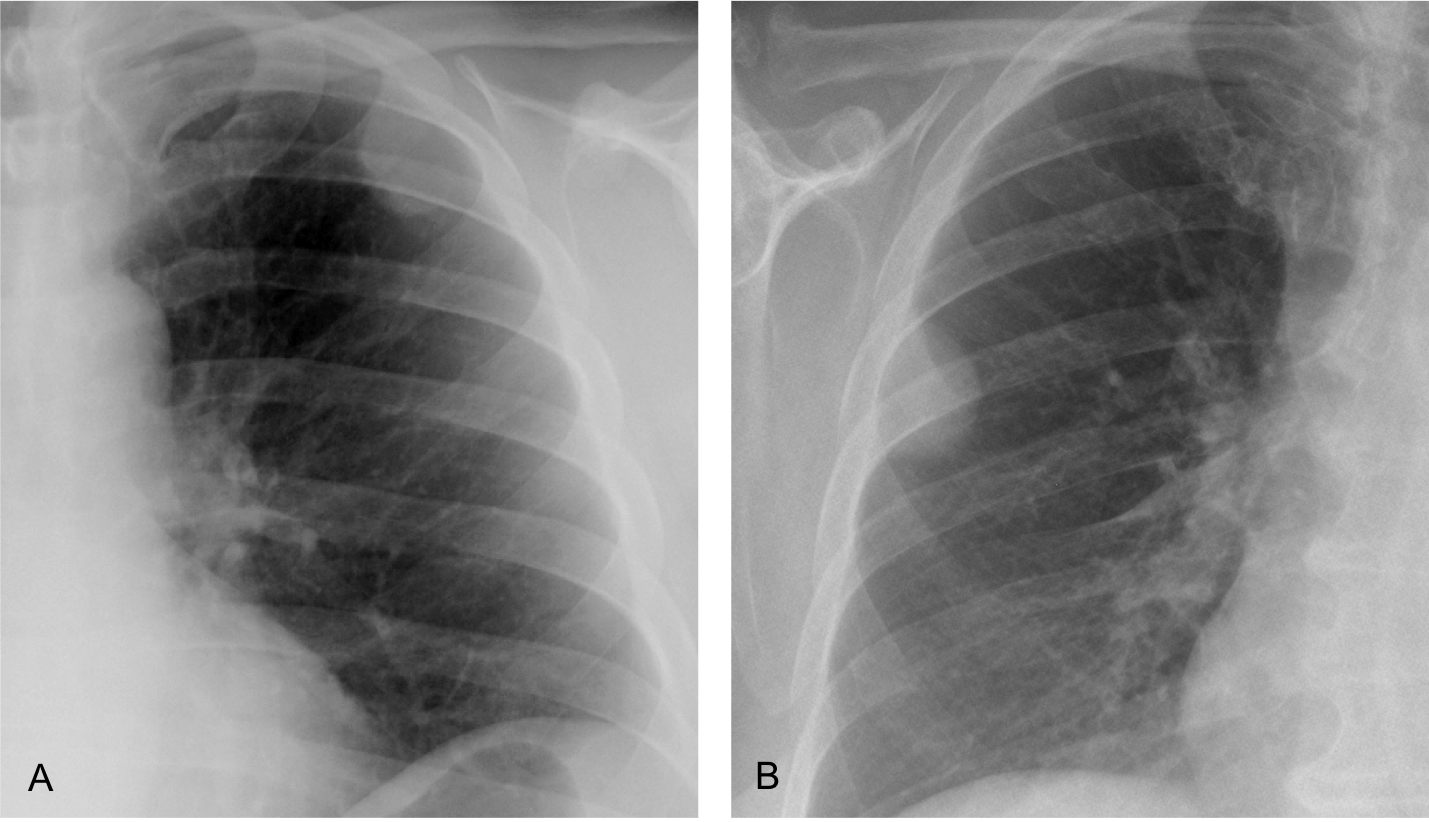

Today’s radiographs belong to two different patients with peripheral opacities of the chest. What would be your diagnosis?

Findings: Radiograph of case A shows an opacity in the left upper lung. Its inner contour is outlined by air (arrow) and the outer border is not visible (asterisk) suggesting an extrapulmonary lesion (incomplete border sign).

CT shows that the opacity represents extrapleural fat (B, arrow).

Radiograph of the second case shows a well-defined rounded opacity (C, arrow), that was interpreted as a peripheral pulmonary nodule. PET-CT was done, and the apparent pulmonary nodule was shown to be extrapleural fat (D, arrow).

These two cases are shown to emphasize that fat in or around the lung cannot be distinguished from soft tissues in the plain chest radiograph. To recognize fat, CT is necessary.